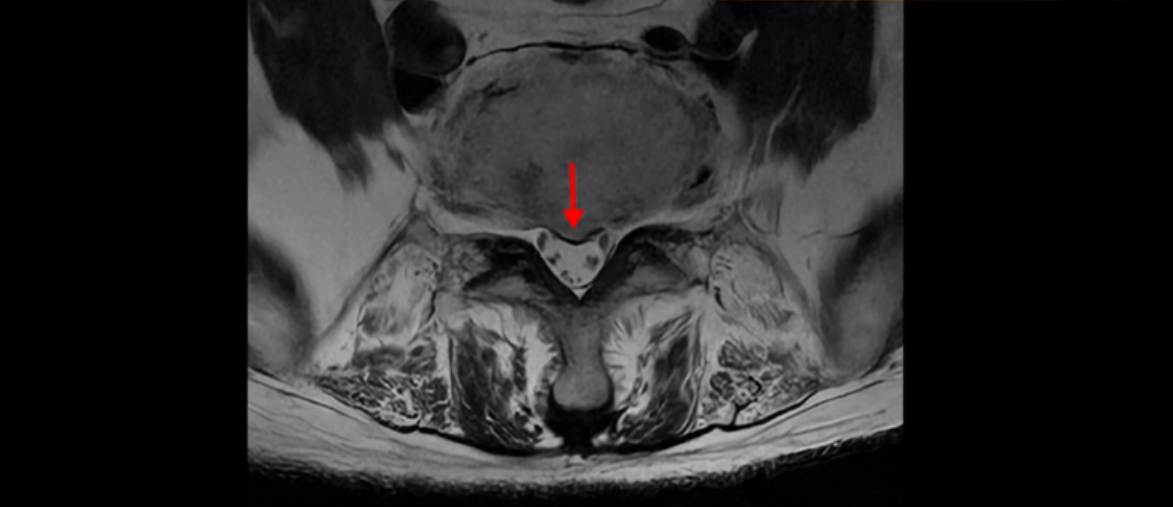

MRI를 보면 허리 4마디가 심하게 퇴행되어 있고

3번 뼈는 넘어질 때 생긴 압박골절이 있습니다.

3번 4번에는 척추관협착과 디스크 탈출이 보이고

4번 5번에는 척추관협착과 심한 디스크 파열이 있습니다.

5번 1번에는 뼈가 자라난 골극이 있고

기립근의 지방화도 심합니다. 또 3번 4번 마디에서는 신경가지가 빠져나가는 추간공이 왼쪽, 오른쪽 모두 많이 좁아져 있습니다.

이런 이유로 이 환자분은 왼쪽 다리는 마비가 생겨 힘이 빠지고 오른쪽 다리에는 심한 방사통이 있어서 휠체어까지 타야 하는 상태가 되었습니다. 이렇게 심하니까 대학병원에서 여러 마디 나사를 박는 유합술을 권유 받으셨는데요.